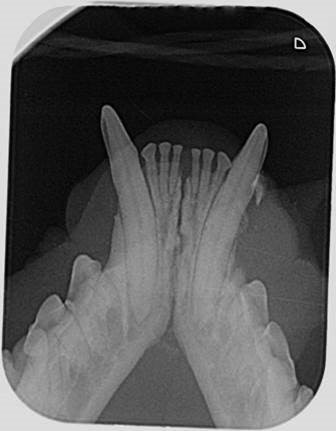

- Im Fall „unserer“ Katze wurde ein abgebrochener Zahn im Oberkiefer entfernt und die Unterkieferfraktur mit Drahrcerclagen fixiert.

stabilisierte Symphysenseparation durch Drahtcerklage

Drahtcerklage im Unterkiefer

zusätzliche Stabilisierung durch eine Drahtcerklage um die Eckzähne

zusätzliche Sicherung mit einer Drahtcerklage um die Eckzähne, übergossen mit Composit

Nach Entfernung der Drahtcerklage